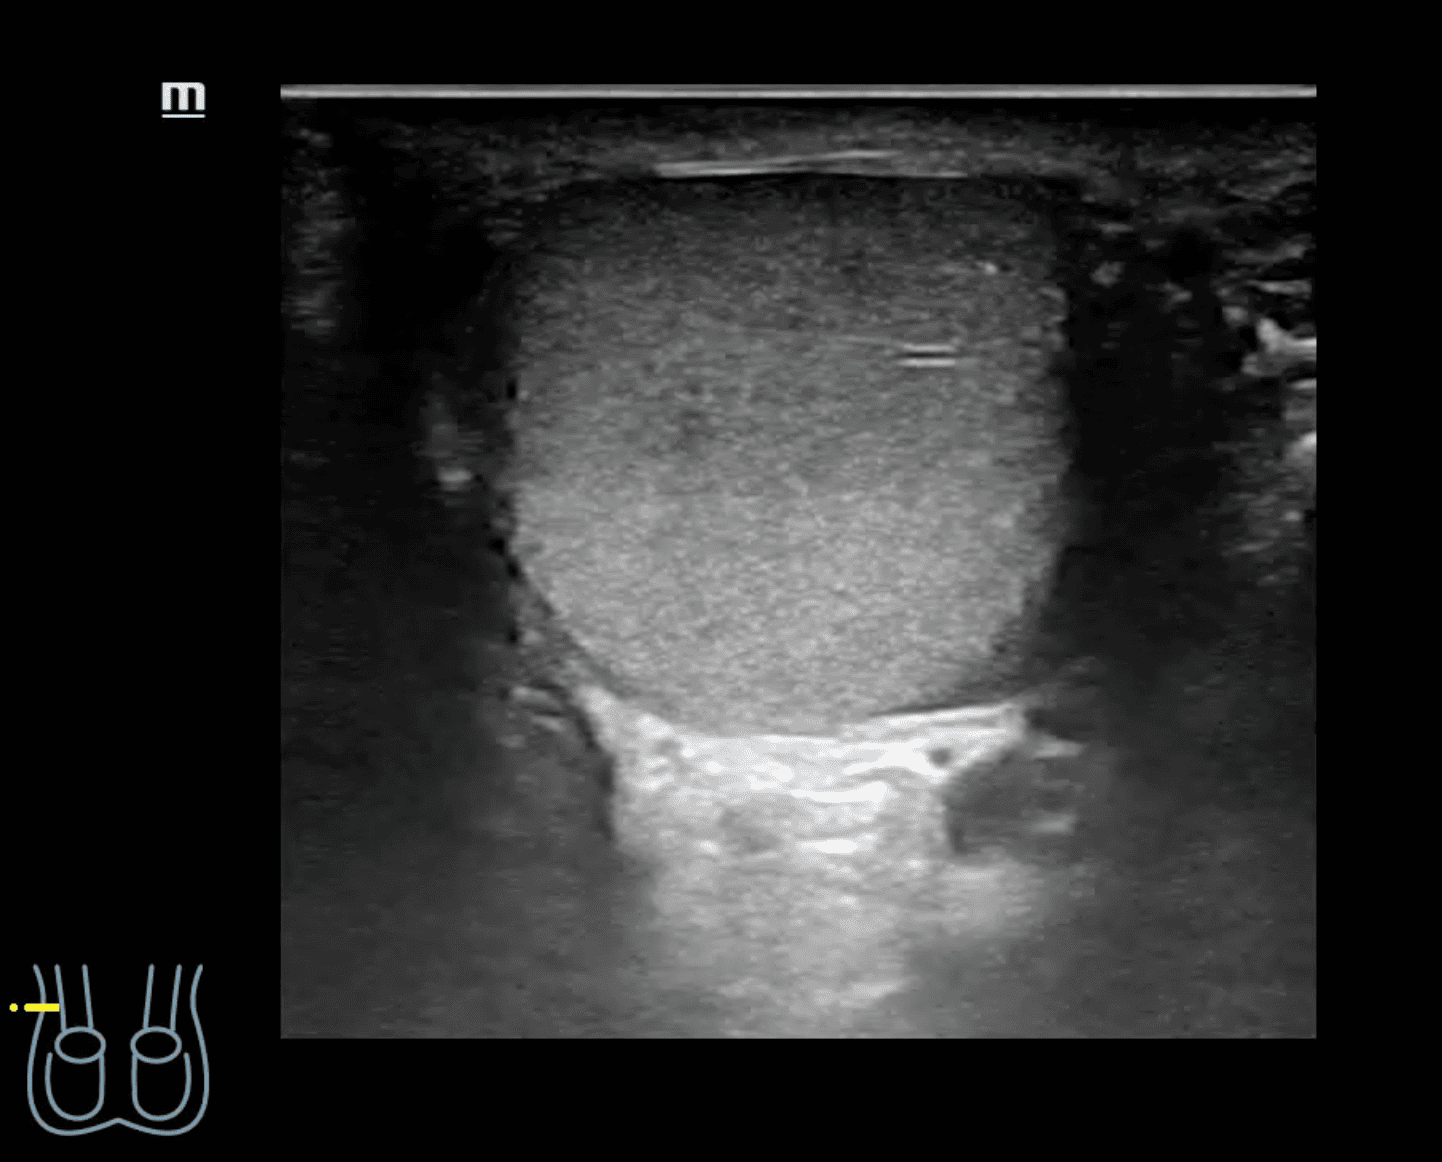

A nivel de escroto derecho, se observa imagen heterogénea con contenido intestinal compatible con hernia inguino-escrotal derecha. Testículos de aspecto normal.

Hernia inguino-escrotal derecha reductible dolorosa, no complicada.